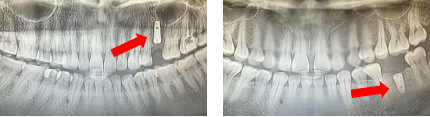

种植患者1年后口内复查照片及X线影像